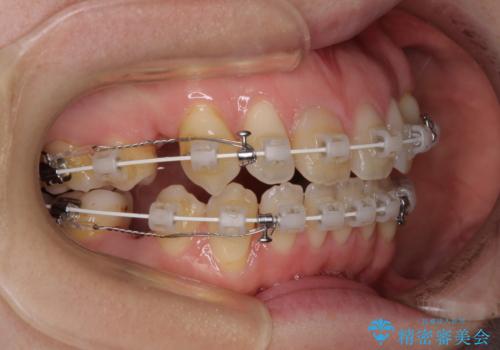

- 矯正装置

- 審美装置

- 治療期間

- 1年9ヶ月

上顎左右第一小臼歯2本、下顎左右第二小臼歯2本を抜歯し、ワイヤー装置にて口元を引っ込めるよう矯正治療を行うこととしました。

上下の前歯に隙間が空くほど上顎前歯が前に飛び出していましたが、抜歯矯正により上下前歯がぴったりと付くほど口元を引っ込めることができました。